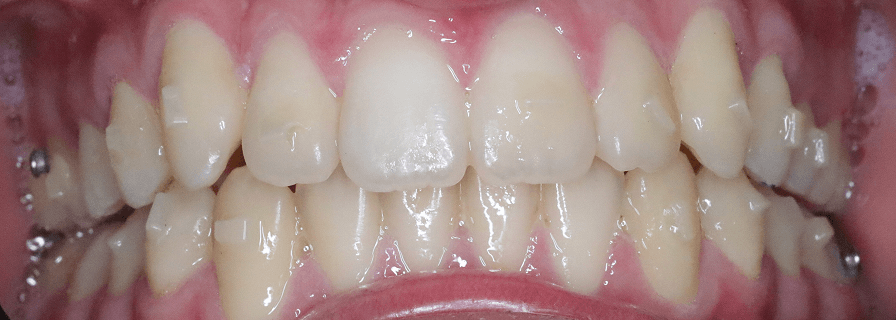

Tratament Ortodontic Fix pentru Înghesuiri Severe

Am tratat cazul cu aparat fix bimaxilar, după o evaluare completă a complexității și a necesarului de spațiu. Cazul a fost finalizat în aproximativ 1 an.